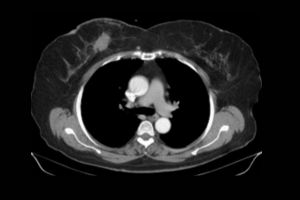

NCCT Temporal Axial and Coronal

Medifyhome offers NCCT Temporal Axial and Coronal scans, a non-contrast computed tomography (NCCT) imaging service for the temporal bone of the skull. This type of scan gives you detailed axial and coronal views of the temporal bones, which protect the inner ear structures and surrounding tissues. Recommended for patients with hearing loss, dizziness, infections, or trauma-related injuries, the NCCT Temporal scan helps to detect and diagnose fractures, infections, or abnormalities that affect balance, hearing, and facial functions. Medifyhome’s service uses advanced equipment and experienced professionals to ensure accurate imaging, so you can trust us for precise diagnostic care. With Medifyhome’s NCCT Temporal Axial and Coronal scans, you get high-quality imaging to support diagnosis and treatment plans.

What is an NCCT Temporal Axial and Coronal Scan?

An NCCT Temporal Axial and Coronal Scan is an imaging diagnostic test, where an X-ray or computed tomography (CT) scan will give a non-contrast two-dimensional view of the image of the temporal bone located inside the skull. A high-resolution scan in axial or coronal view allows health workers to assess inner ear structures efficiently. The main clinical condition diagnosed by this scanning tool is fracture, infections, and other abnormalities involving an impairment in hearing or maintaining balance. This makes the scan a very useful tool in the diagnosis and treatment of patients with otologic or neurologic disorders.